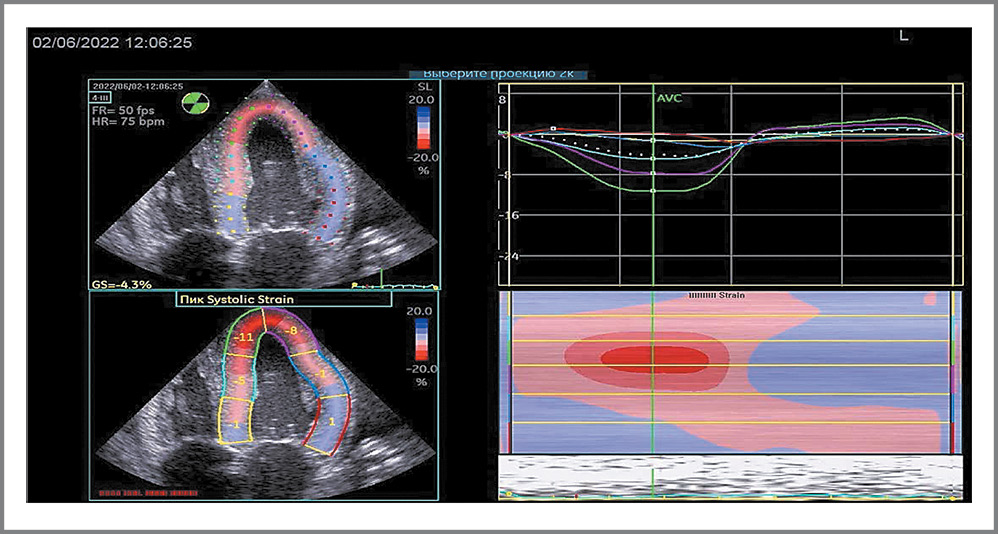

Инструментальные исследования. ЭхоКГ-исследование проведено на аппарате экспертного класса General Electric Vivid iq в ФГБНУ НИИ КПССЗ (см. табл. 1). Дополнительно, к ранее представленным данным, отмечалось снижение ФВ до 39%, а также «свечение» миокарда с гиперэхогенными включениями (рис. 2). Согласно современным рекомендациям [9] использована технология Speckle Tracking с оценкой деформации миокарда, по результатам которой выявлена типичная картина для амилоидоза сердца – выраженное снижение деформации средних и базальных сегментов ЛЖ с сохраненной деформацией верхушечных сегментов (рис. 3, 4). Показатель GLS (глобальной продольной деформации) снижен до -4,4%, через 14 дней он снизился до -3,6% (см. табл. 1). По УЗИ плевральных полостей – двусторонний гидроторакс (слева – 12 см, справа – 7,6 см). В рамках госпитализации магнитно-резонансную томографию с контрастированием гадолинием не проводили по техническим причинам.

Рис. 3. Технология Speckle Tracking ЭКГ, апикальное сечение. Выраженное снижение деформации средних и базальных сегментов ЛЖ (голубой и розовый цвета) с сохраненной деформацией верхушечных сегментов (красный цвет)

Fig. 3. Speckle Tracking echocardiography technology, apical section. Pronounced reduction in deformation of the middle and basal segments of the left ventricle (blue and pink) with preserved deformation of the apical segments (red)

Рис. 4. Технология Speckle Tracking ЭКГ в виде «бычьего глаза»

Fig. 4. Speckle Tracking echocardiography technology in the form of a "bull's eye"